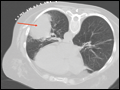

| Figure e34-6 Apical scarring, traction bronchiectasis (red arrow), and decreased lung volume consistent with previous tuberculosis infection. Findings most significant in left lung. | |